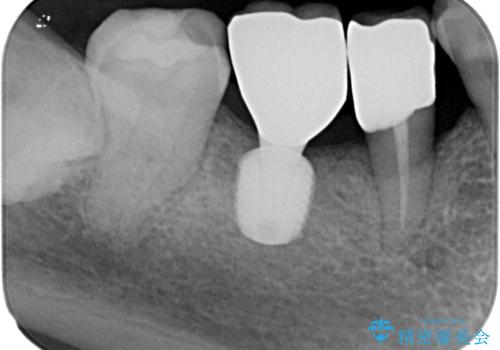

- 奥歯を抜歯してから放置しているとのことで来院された患者様です。

地元の歯科医院では、インプラント補綴治療かブリッジによる治療の二択を提示され、悩んでいらっしゃる状態でした。

歯が割れて抜歯になってしまったとのことと、ブリッジの土台となる手前の歯は既に神経が取り除かれていて、こちらも破折するリスクが高いことから、咬合力に抵抗できるよう、インプラントによる補綴治療を行うこととしました。

手前の神経を取り除いている歯も、合わせて補綴治療を行うこととしました。